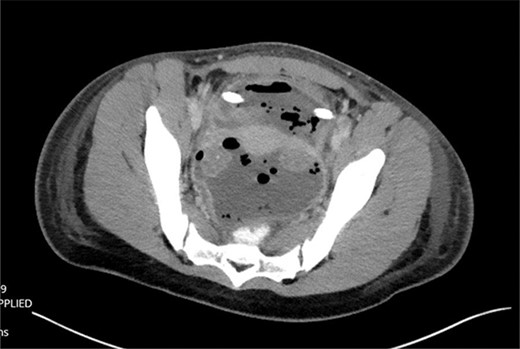

The patient developed abdominal pain with associated leukocytosis with left shift, which prompted a CT of the abdomen and pelvis on postop Day 4 with evidence of moderate to large amount of ascites and a large amount of scattered pneumoperitoneum (Fig. 2).

CT imaging with evidence of ascites and scattered pneumoperitoneum.